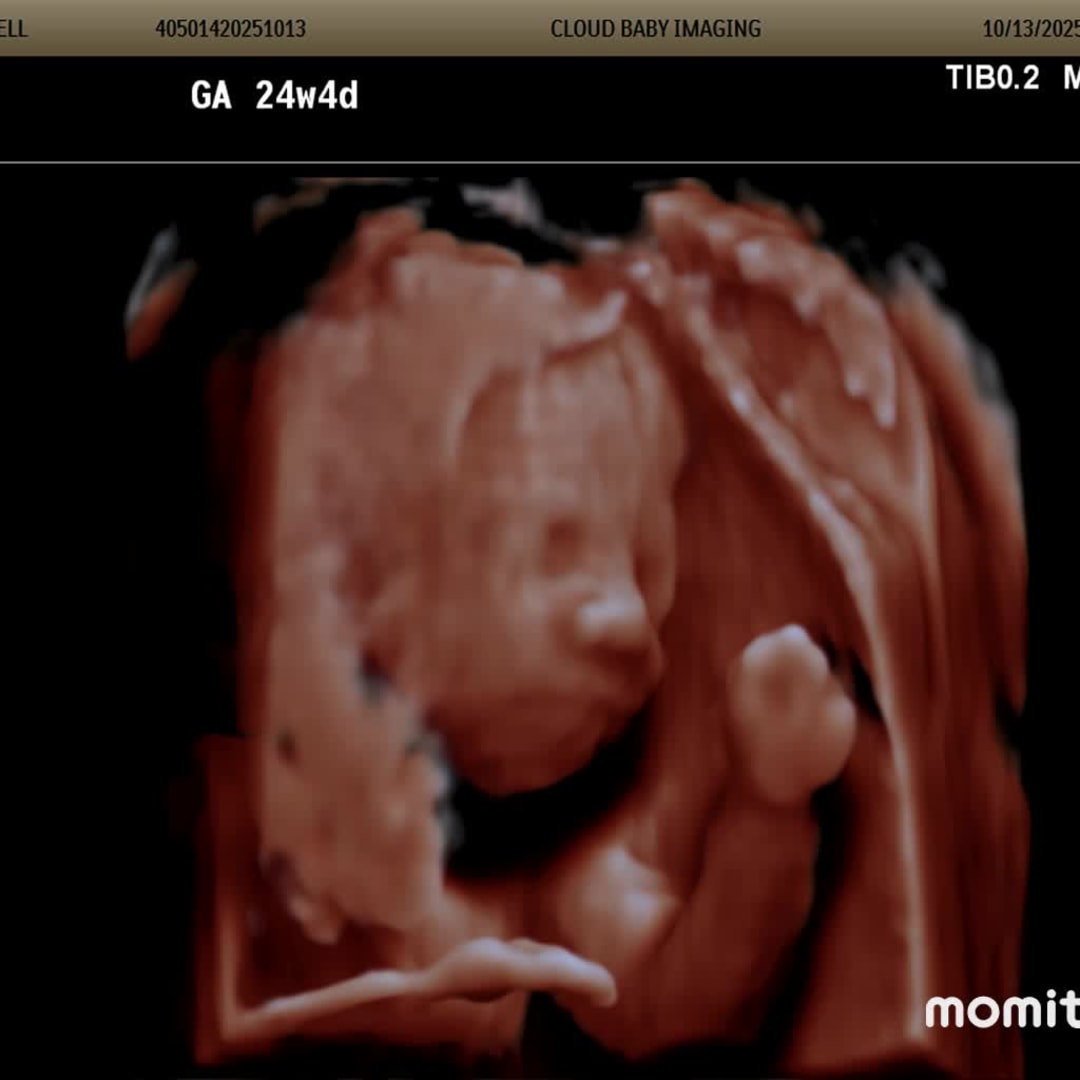

Wren’s Selfies